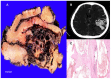

Vascular malformations are frequent in the head and neck region, affecting the nervous system. The wide range of therapeutic approaches demand the correct anatomical, morphological, and functional characterization of these lesions supported by imaging. Using a systematic search protocol in PubMed, Google Scholar, Ebsco, Redalyc, and SciELO, the authors extracted clinical studies, review articles, book chapters, and case reports that provided information about vascular cerebral malformations, in accordance with Preferred Reporting Items for Systematic Reviews and Meta-Analyses (PRISMA) guidelines. A total of 385,614 articles were grouped; using the inclusion and exclusion criteria, three of the authors independently selected 51 articles about five vascular cerebral malformations: venous malformation, brain capillary telangiectasia, brain cavernous angiomas, arteriovenous malformation, and leptomeningeal angiomatosis as part of Sturge-Weber syndrome. We described the next topics-"definition", "etiology", "pathophysiology", and "treatment"-with a focus on the relationship with the imaging approach. We concluded that the correct anatomical, morphological, and functional characterization of cerebral vascular malformations by means of various imaging studies is highly relevant in determining the therapeutic approach, and that new lines of therapeutic approaches continue to depend on the imaging evaluation of these lesions.